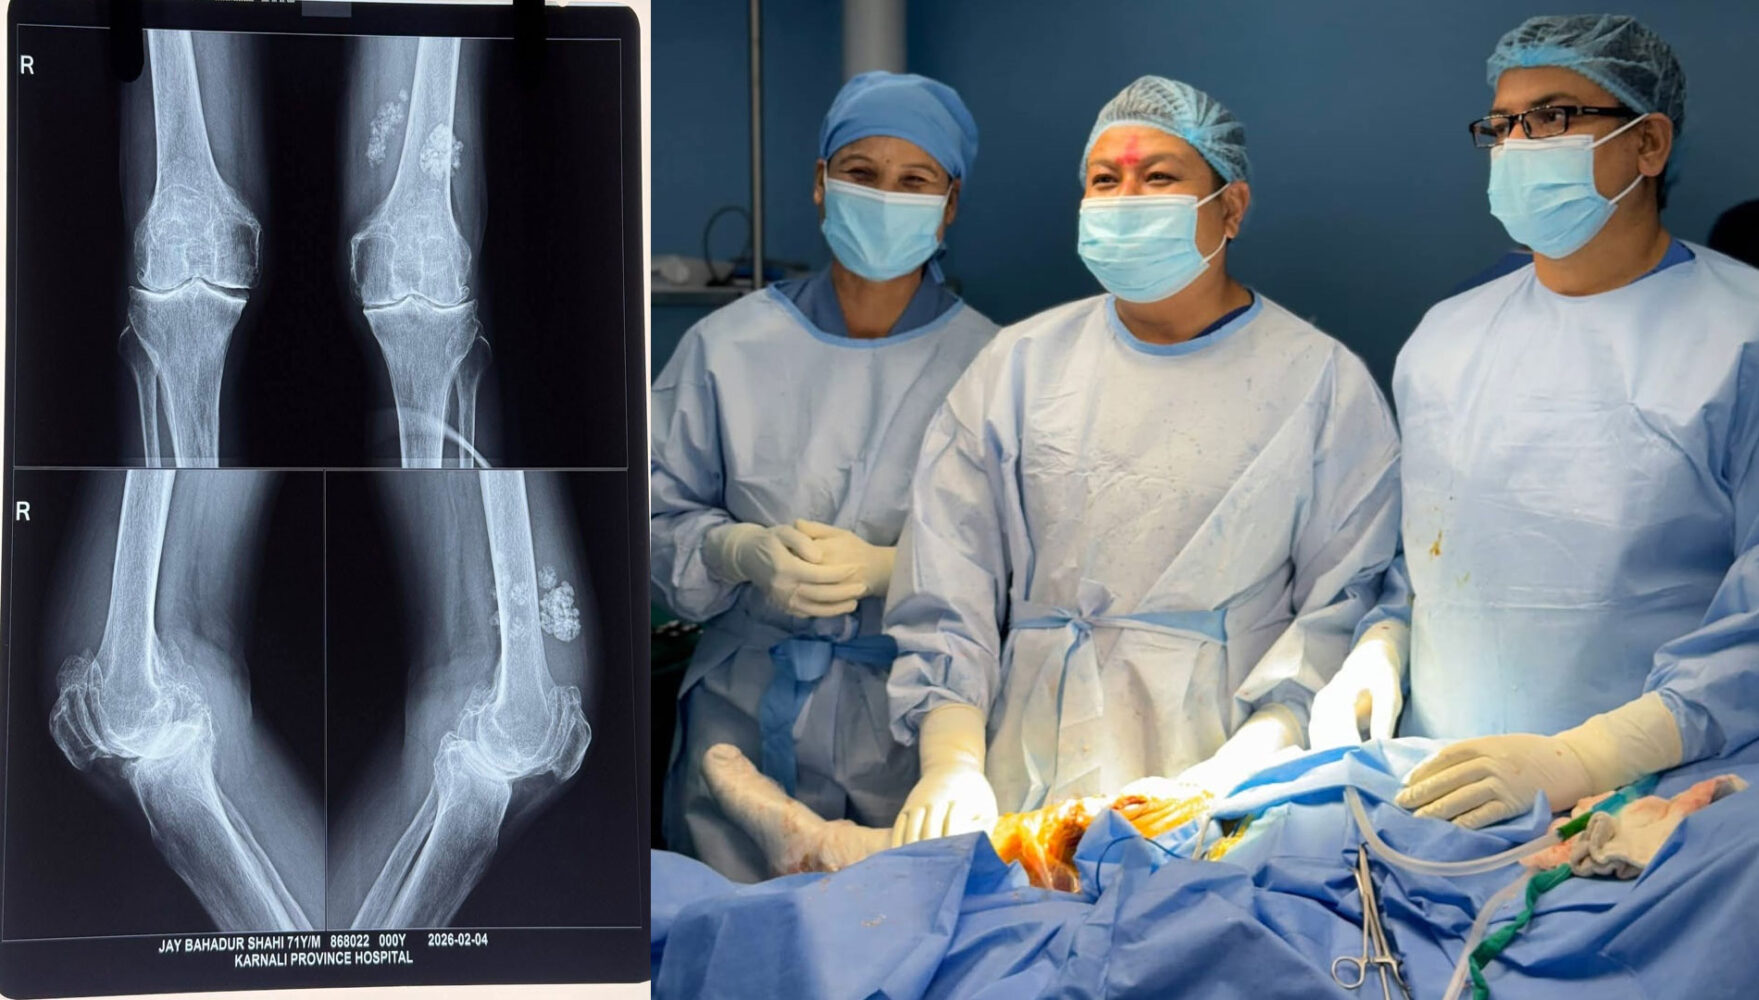

सुर्खेत । प्रदेश अस्पतालले जटिल मानिने ‘कृत्रिम घुँडा प्रत्यारोपण’ (Knee Replacement) शल्यक्रिया सफलतापूर्वक सम्पन्न गरेको छ। प्रदेश अस्पतालका चिकित्सकहरूले कम्मरको जोर्नी खिइएर दैनिक क्रियाकलाप गर्न समेत सास्ती भोगिरहेका बिरामीहरूको पाँचौँ पटक सफलतापूर्वक शल्यक्रिया गरेका हुन् । प्रदेश अस्पतालका चिकित्सक पदम गिरीका अनुसार कर्णाली प्रदेशमै पहिलो पटक गरिएको यो जटिल शल्यक्रिया गरिएकाे हाे । याेसँगै चिकित्सा सेवालाई नयाँ उचाइमा पुर्याएको छ। यसले कर्णालीको स्वास्थ्य क्षेत्रमा एउटा सुखद र गर्विलो अध्याय थपिएको चिकित्सककाे भनाइ छ। दक्ष जनशक्ति टिकाइ रहने र उपकरणकाे दीर्घकालीन प्रयाेग गर्न सकेकाे खण्डमा अब जटिल हाडजोर्नी सम्बन्धी उपचारका लागि काठमाडौँ वा छिमेकी मुलुक धाउनुपर्ने बाध्यताको अन्त्य हुने छ । याे सेवा लामो समयदेखि घुँडा खिइएर हिँडडुल गर्न अक्षम बिरामीका लागि यो सेवा वरदान सावित हुने छ।

अत्याधुनिक प्रविधि र दक्ष चिकित्सकको टोलीले प्रदेशमै पहिलो पटक कृत्रिम घुँडा सफल प्रत्यारोपण गरेर कर्णालीको स्वास्थ्य सेवामा एउटा नयाँ रेकर्ड कायम गरेको छ। यसैगरी, अस्पतालले कम्मरको जोर्नी (Hip Joint) खिइएका बिरामीहरूको पनि सफल उपचार गरिरहेको छ । हिँडडुल गर्न र सामान्य काम गर्न नसक्ने अवस्थाका बिरामीहरू अब नयाँ जीवन पाए झैँ सक्रिय हुन थालेका छन्।